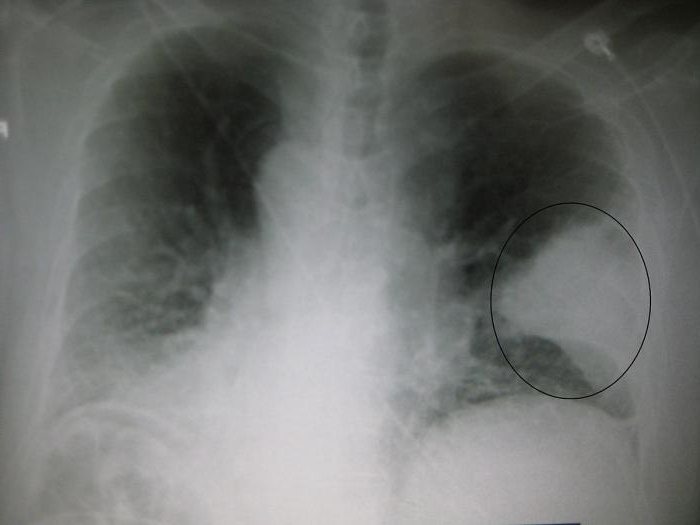

Для подтверждения диагноза используется рентгенологическое исследование органов грудной клетки (обнаруживаются очаговые инфильтраты). Лабораторные исследования помогают определить тяжесть течения болезни и результативность антибактериальной терапии, но не являются ведущими при постановке диагноза.

- рентгенологического исследования в двух проекциях (для определённых видов возбудителей характерна своя картина на снимке);

Если состояние пациента не улучшилось после назначенной терапии, и на рентгенограмме есть очаги нетипичной для внебольничной пневмонии локализации, то можно заподозрить атипичную пневмонию.

Исследование мокроты